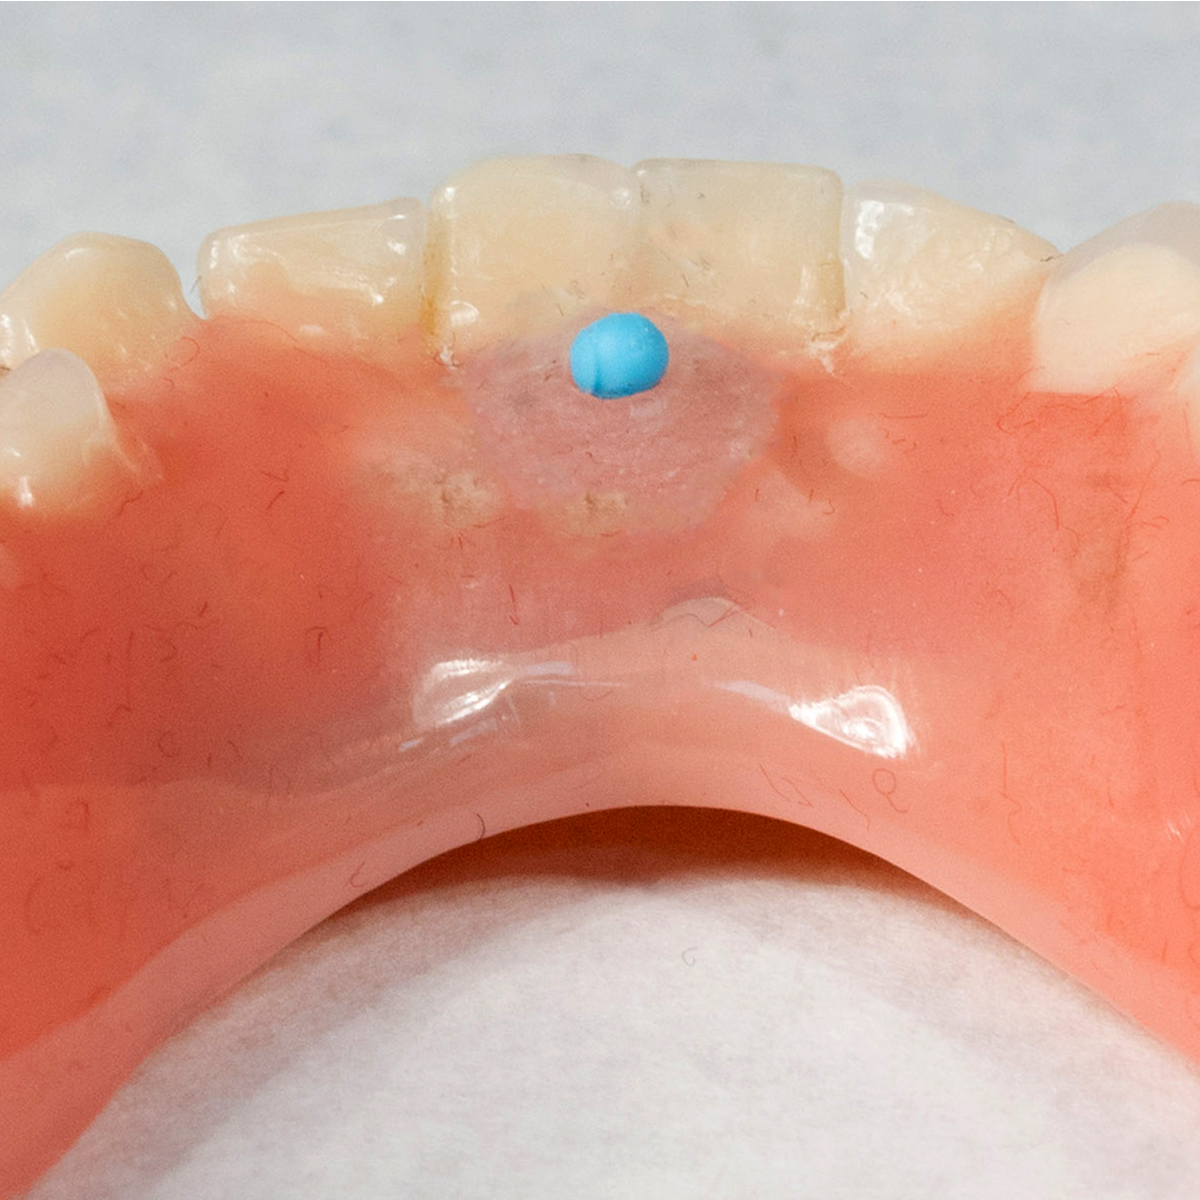

(2.) Tissue conditioning materials functionally adapted to the denture to promote recovery of denture bearing soft tissues.

Figure 2

(3.) Gothic arch tracer assembly attached to the maxillary and mandibular dentures in preparation for fabrication of occlusal device.

Figure 3

(13.) Placing a training bead on the lingual aspect of the denture in between the central incisors will help retrain the retracted tongue.

Figure 13

(14.) Placing a dyed resin bump further helps with the development of a normal tongue posture by inducing visual memory.

Figure 14